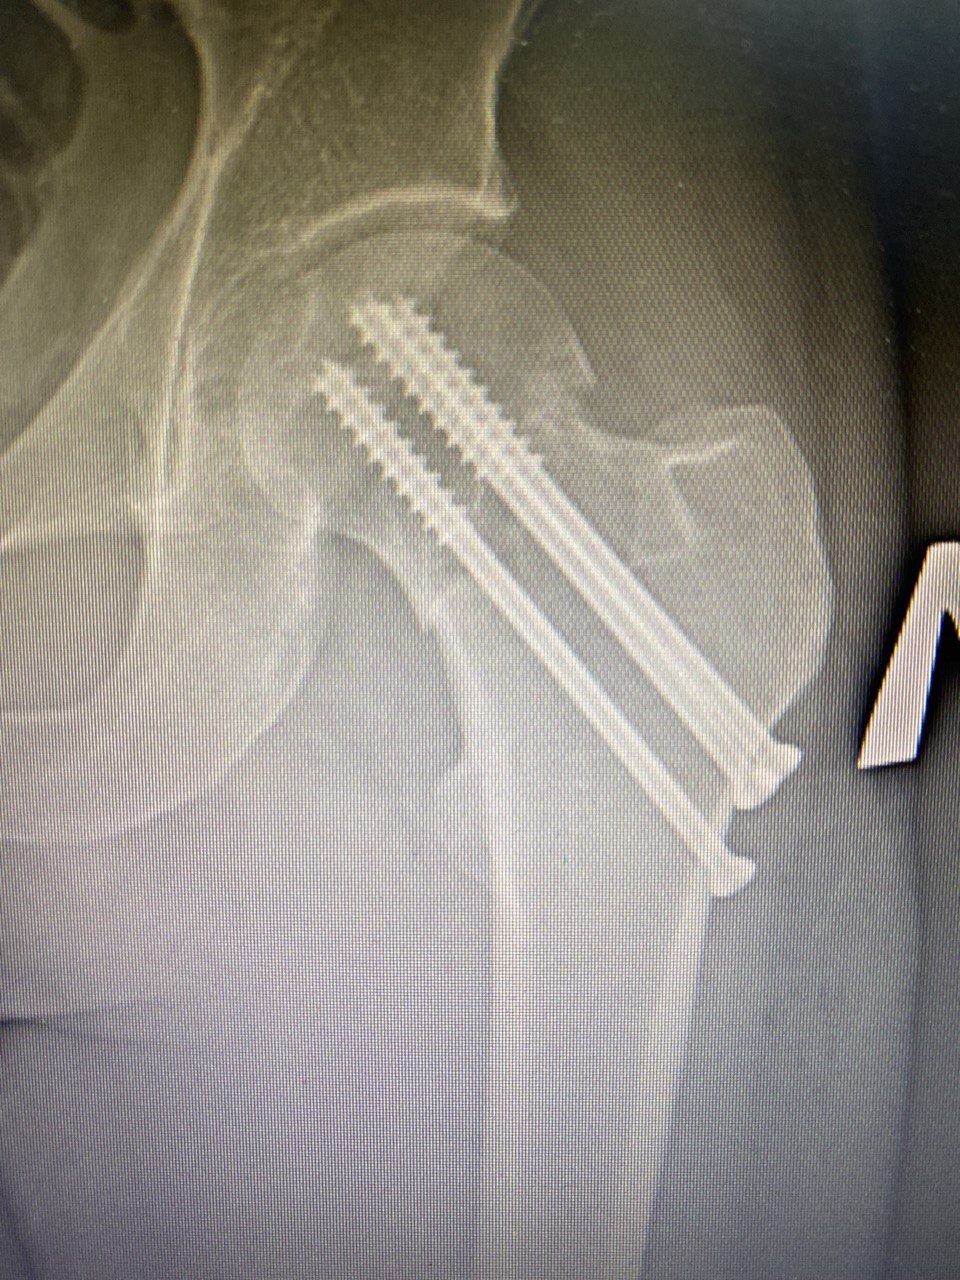

Шейка бедра — звучит, как сытное мясное блюдо из меню ресторана за углом, но на самом деле это наша «деталь». Причем очень важная, так как при ее патологии человек не может ходить, поэтому перелом шейки бедра — всегда трагедия. И произойти она может с каждым, просто в молодом возрасте, как правило, этому предшествует высокоэнергетичная травма, такая как ДТП или падение с высоты. Например, на фото слева — снимок шейки бедренной кости пациента (39 лет), который попал в аварию. Пациент поступил ко мне в день ЧП с изолированным переломом шейки бедра.

После обследования пациента было принято решение о проведении операции остеосинтеза (скрепления частей) шейки бедра винтами. Причем сделали мы это без разрезов! Дело в том, что в нашей операционной есть электронно-оптический преобразователь (ЭОП) — специальный цифровой рентген. С его помощью на протяжении всей операции мы делали снимки, выводили их на экран и тем самым контролировали каждое действие, даже работая через маленькие проколы.

После операции восстановление пациента прошло гладко, а уже через 2 месяца на снимке мы увидели, что костные ткани срослись и перелома больше нет.